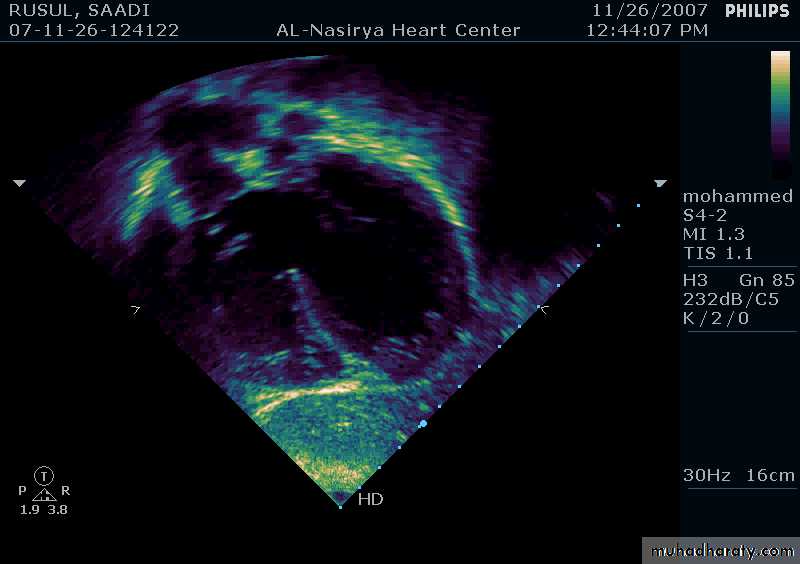

33Echocardiography & TEE

Shows the size of the defectThe direction of blood flow

The pulmonary artery pressure34

Ostium Secundum ASD

35